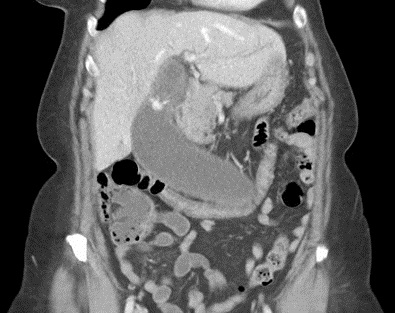

Image radiologique TDM

, contrast intraveineuse en coupe coronal : Se

presente une cholecystite aigue avec deux

calculs de la vesicule biliaire . Sa paroi est

epais , oedeme |

|